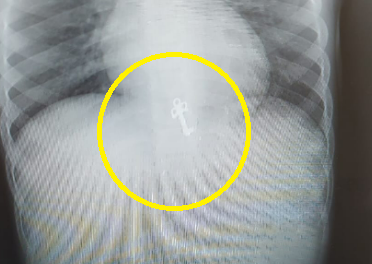

בצילום חזה, מצא רופא הילדים ד"ר חגי שטרן את המפתח הזעיר כשהוא בקיבתו של התינוק. היותו של המפתח משונן ודוקרני חייב פעילות פולשנית של הוצאת המפתח מחשש לסיכון ולקרע במעבר למעי, ובשל כך הועבר התינוק לחדר ניתוח בבית החולים.